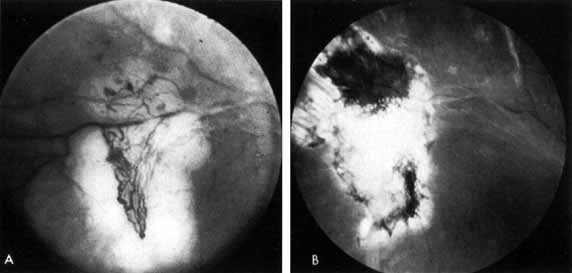

As demonstrated by increased latency and decreased amplitude of the visual evoked potential, many patients with diabetes without retinopathy have subclinical optic neuropathy.269,270 In addition, patients with diabetes can develop two types of acute optic neuropathy. The first, anterior ischemic optic neuropathy (AION) is identical to that seen in patients without diabetes. The patients report a sudden decrease in visual acuity or a sudden visual field loss.271–273 The main ocular finding is a “pale swelling” of the optic nerve head with, considering the degree of disc edema, very few hemorrhages (Fig. 27). On fluorescein angiography segmental nonfilling or slow filling is seen (Fig. 27). An afferent pupillary defect (Marcus Gunn) is nearly always present. Visual fields commonly show altitudinal or nerve fiber bundle defects. The disc progresses to optic atrophy (Fig. 27), and improvement in visual function is rare.

Fig. 27 A. Right eye: ischemic optic neuritis. Note pale swelling of optic disc and blurring of disc margins. Left eye: normal disc. B. Fluorescein angiogram. Note poor filling on disc inferotemporally as compared with the rest of the disc. C. Right eye 6 months after optic neuritis. Note slight pallor.